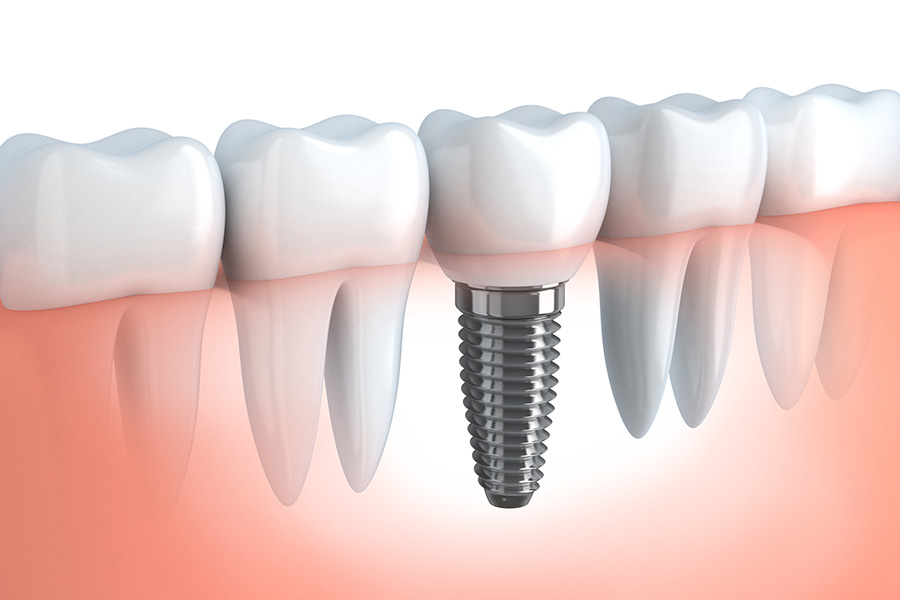

インプラントIMPLANT

インプラント治療は、失ってしまった歯の部分に人工の歯根(チタン製のインプラント)を埋め込み、その上に人工の歯を装着する方法です。

天然の歯と同じようにしっかりと噛むことができ、見た目も自然で、美しい口元を保つことができます。

従来の入れ歯やブリッジと異なり、周囲の健康な歯を削る必要がなく、違和感も少ないのが大きな特徴です。

食事や会話を快適に楽しめるようになり、生活の質の向上にもつながります。

当院では、精密検査を行い、患者さま一人ひとりの骨や歯ぐきの状態を詳しく診断したうえで、安全で適切な治療計画をご提案いたします。治療後も定期的なメンテナンスを行い、長く安心してお使いいただけるようサポートいたします。